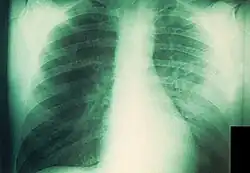

La peste neumónica tiene dos formas, primaria y secundaria, frecuentemente mortales y potencialmente contagiosas para los contactos cercanos.[48][49] Es más común la secundaria, causada por la diseminación hematógena de la bacteria desde el bubón u otra fuente. Aproximadamente el 10 % de los enfermos de peste en los Estados Unidos desarrollan peste neumónica secundaria, habitualmente por el retraso en el tratamiento de la forma bubónica. Comienza como un proceso intersticial con tos productiva y esputo escaso, que normalmente comienza cinco o seis días después de los primeros síntomas. La radiografía de tórax revela infiltrados alveolares difusos casi siempre bilaterales y acompañados de derrame pleural.[50] Sin tratamiento, el esputo se vuelve más copioso y, finalmente, sanguinolento; la muerte ocurre frecuentemente a los tres o cuatro días.[4]

La forma primaria de la peste neumónica es un cuadro fulminante que resulta de la inhalación directa de la bacteria en los pulmones. Puede ocurrir al haber estado en contacto con otra persona con peste neumónica, exposición a animales con peste respiratoria o faríngea (especialmente gatos), infección en el laboratorio o, potencialmente, consecuencia de la liberación intencional de aerosoles con propósitos terroristas. Los síntomas comienzan entre uno y cuatro días después de la exposición; se instauran velozmente e incluyen fiebre, escalofríos, cefalea, malestar, signos generales de endotoxemia, taquipnea, disnea, hipoxia, dolor torácico, tos y hemoptisis. La radiografía de tórax muestra al principio una neumonía lobar que evoluciona a una consolidación densa y diseminación broncopulmonar a otros lóbulos del pulmón ipsilateral o contralateral.[36][51] Normalmente, el esputo es purulento, aunque también puede ser acuoso, espumoso y copioso; asimismo, es posible que presente algo de sangre o que sea francamente hemorrágico, en cuyo caso podría contener grandes cantidades de bacilos.[48] En cuanto a la histología, el espacio alveolar se muestra lleno de bacterias y células inflamatorias.[43] La enfermedad casi siempre es letal sin tratamiento y la mortalidad es también alta cuando este se demora más de 24 horas tras el comienzo de los síntomas. Más o menos, el 25 % de los afectados por peste neumónica en los Estados Unidos desde 1950 han fallecido.[4]